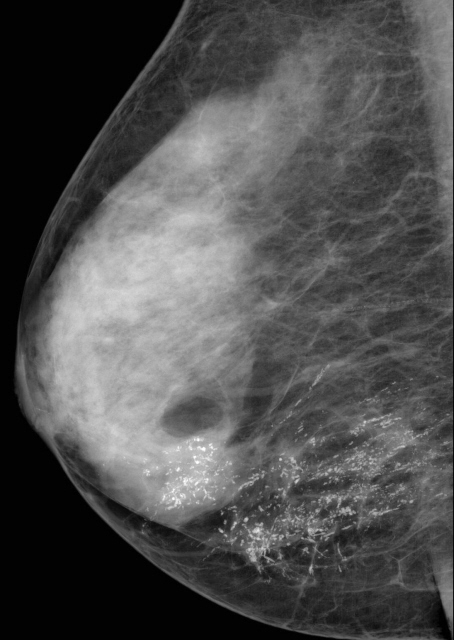

УЗИ молочных желез — информативный и безопасный метод диагностики, с помощью которого можно точно оценить состояние желез, обнаружить доброкачественные и злокачественные образования, уточнить диагноз. Это доступное по цене исследование безвредно и не несет лучевой нагрузки. Оно имеет большое значение в ранней диагностике заболеваний и нередко применяется в профилактических целях. На УЗИ может направить маммолог, онколог, эндокринолог, гинеколог.

Сделать УЗИ молочных желез можно в качестве первичной диагностики и для уточнения уже предполагаемого диагноза. Метод основывается на способности высокочастотных ультразвуковых волн с различной скоростью отражаться от тканей с разной плотностью.

С помощью ультразвуковой диагностики можно обнаружить следующие заболевания:

- воспалительные заболевания — мастит, абсцессы, лактостаз у кормящих женщин, мастопатии различного происхождения и типа — фиброзно-кистозные, диффузные и пр.;

- врожденные аномалии молочной железы;

- рак;

- кисты и доброкачественные опухоли;

кальцинаты.

Для оценки кровотока в тканях молочных желез используется доплерография. Данные, полученные в результате биопсии под контролем УЗ-аппарата, могут сказать о природе и характере образований в молочных железах.